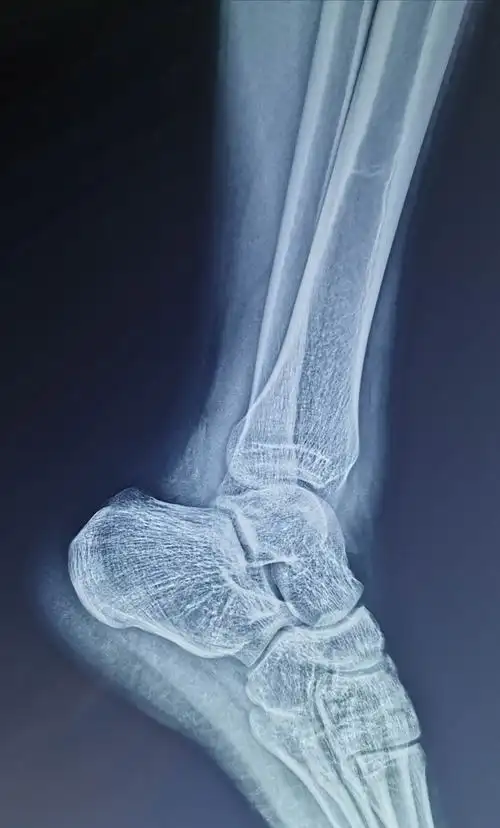

一例腓骨下极撕脱骨折 - 美篇